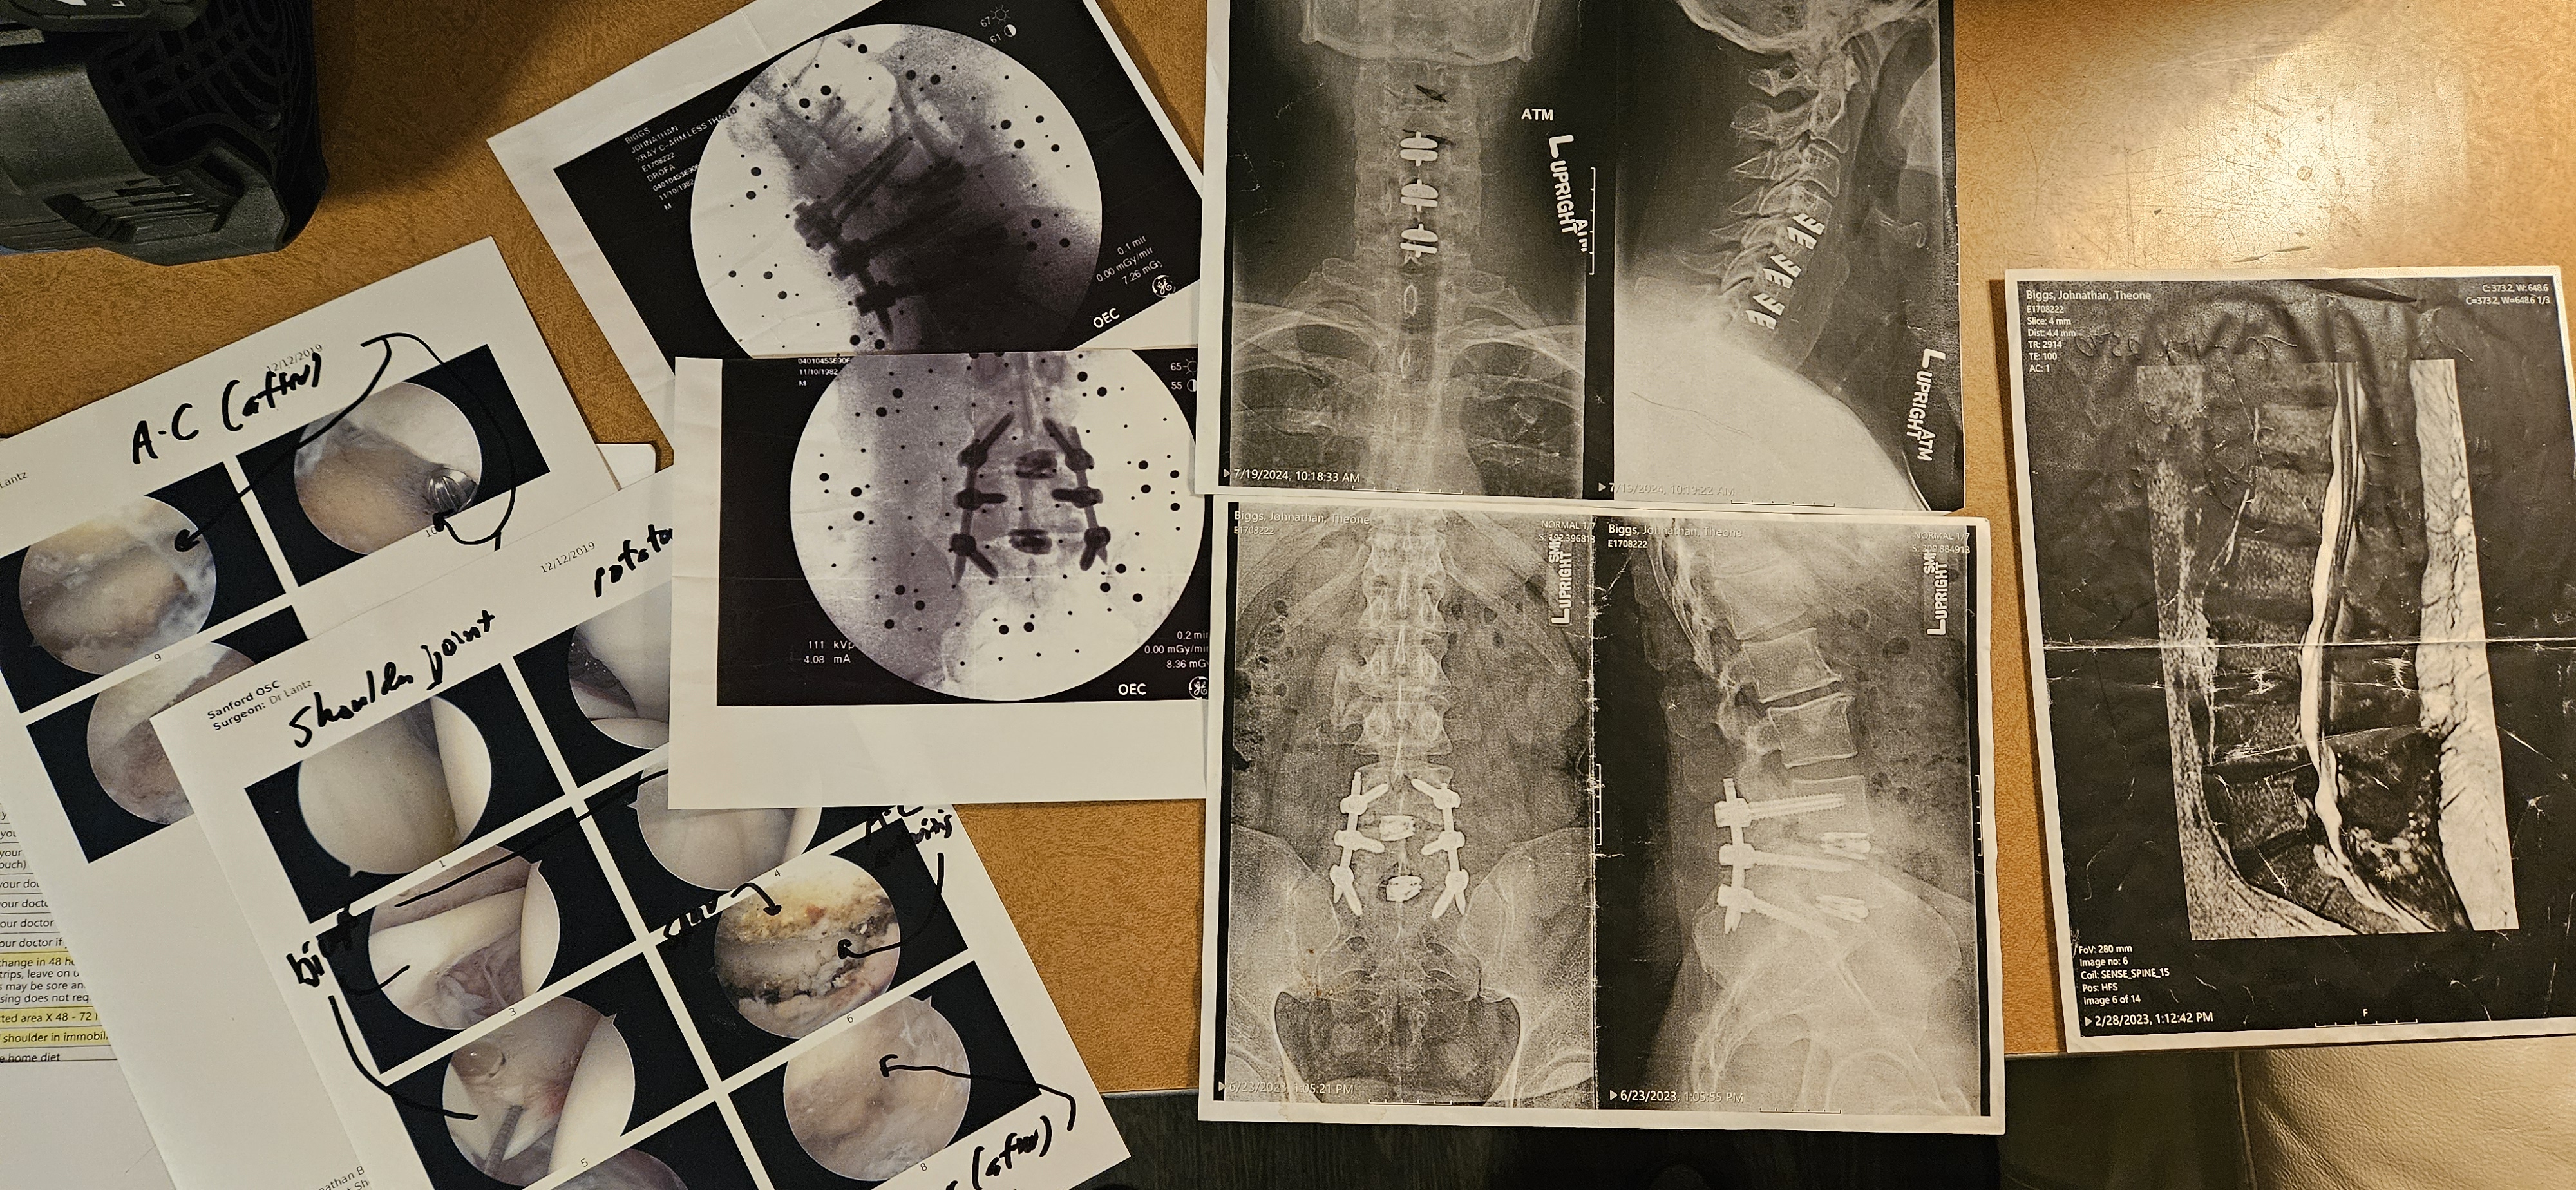

Hello, friends, family, and kind strangers. My name is John Biggs, and I'm reaching out from Fargo, North Dakota, with a heavy heart but hopeful spirit. For years, I've been battling severe back and neck issues that have turned my life upside down. What started as chronic pain from an injury escalated into a series of surgeries—I've undergone multiple procedures on my spine, including fusions and disc replacements, to try and regain some mobility and relief. Each surgery came with its own set of challenges: long recovery times, physical therapy, and mounting bills that I simply couldn't keep up with on my limited disability income.